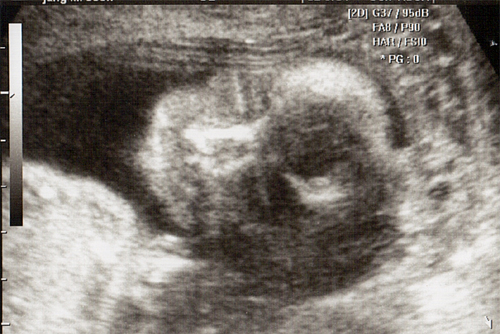

강아 ^^ 21주 강이의 정밀 초음파를 봤어 일반 초음파 보다는 더 정밀하게 나오더라구 엄청 커버린 강이가 한눈에 보이지 않을정도로 이제는 초음파 기계가 작아 보이더라..

강이 얼굴을 딱~ 보는순간.. 심장이 멈추고 코를 보는순가 다시 심장이 뛰기 시작했어 딱.. 아빠 코를 닮았더라 ^^:.. 이쁜자식...